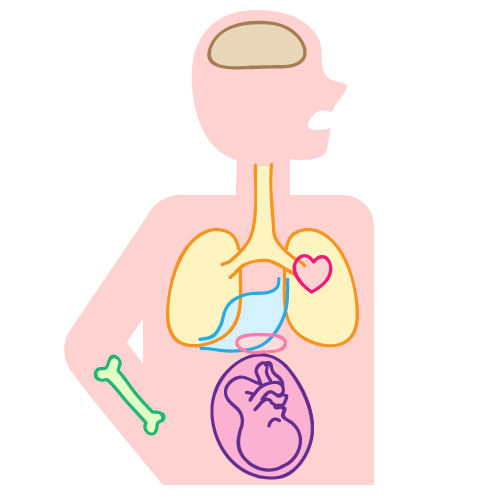

歯周病と全身に及ぼす影響

歯周病は、お口の中の問題だけに留まらず、以下のような全身の病気との関係も指摘されています。

糖尿病

歯周病菌が血液に乗って全身へ広がると、歯周病菌が持つ成分TNFαがインスリンの働きを弱めます。インスリンは血糖値をコントロールするホルモンですので、働きが弱まることで、食後に上昇した血糖値が下がりにくくなります。

肺炎

歯周病菌を含んだ唾液が肺に侵入すると、炎症を起こして肺炎になることがあります。特に嚥下機能の低下が見られるご高齢の方は要注意です。

心臓血管疾患

血液中の歯周病菌が動脈壁に付着すると、小さな血の塊が形成されます。心臓血管疾患の一部は、その塊が心冠動脈に詰まって起こっているという指摘があります。

細菌性心内膜炎

心臓の弁に異常がある方、人工弁を使用している方は、血液に乗った歯周病菌が心臓の内膜で増殖し、心内膜炎を発症することがあります。